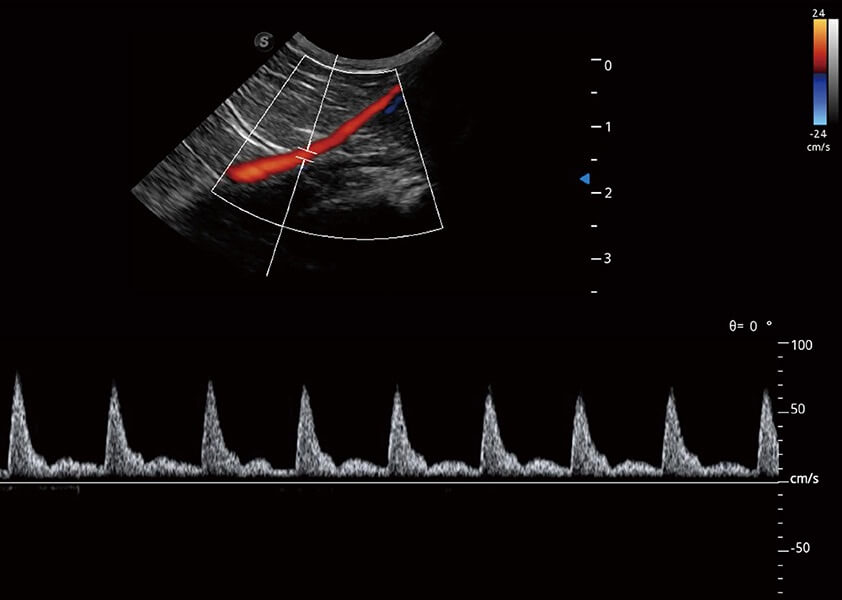

ProPet 60 作为一款高端台式动物超声设备,为动物医生的日常诊断提供了一系列贴合动物临床需求、解决临床实际问题的高级成像功能。凭借全系列高清探头,满足医生对腹部、心脏、生殖、浅表、肌骨等成像的所有需求,切实帮助您提升检查效率,提高诊断信心。

动物是人类最亲密的朋友和最值得信赖的伙伴。哈哈体育官网也一直致力于探索动物专用的超声影像解决方案。 全新推出的ProPet系列,是哈哈体育官网在动物超声影像智能化、专业化、精准化的一次跨越式革新。动物不能用言语来表述自己的不适,通过超声影像,ProPet系列搭建了动物医生与不同物种沟通的“桥梁”,为动物医生注入了“治愈之力”。